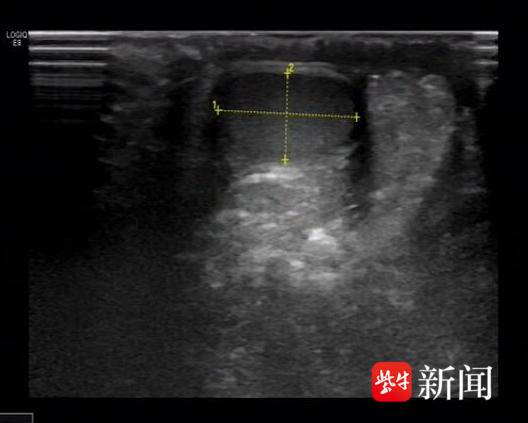

右侧正常*丸睾**

我们都知道,正常男性有双侧*丸睾**,1岁的洋洋为何只能摸到一侧*丸睾**,另一个去哪儿了呢?超声检查给出了答案,B超提示:左侧阴囊内未见*丸睾**回声,于左侧腹股沟区体表标记处见*丸睾**回声。没错,这枚消失的“蛋蛋”,就悄悄躲在腹股沟那儿呢!